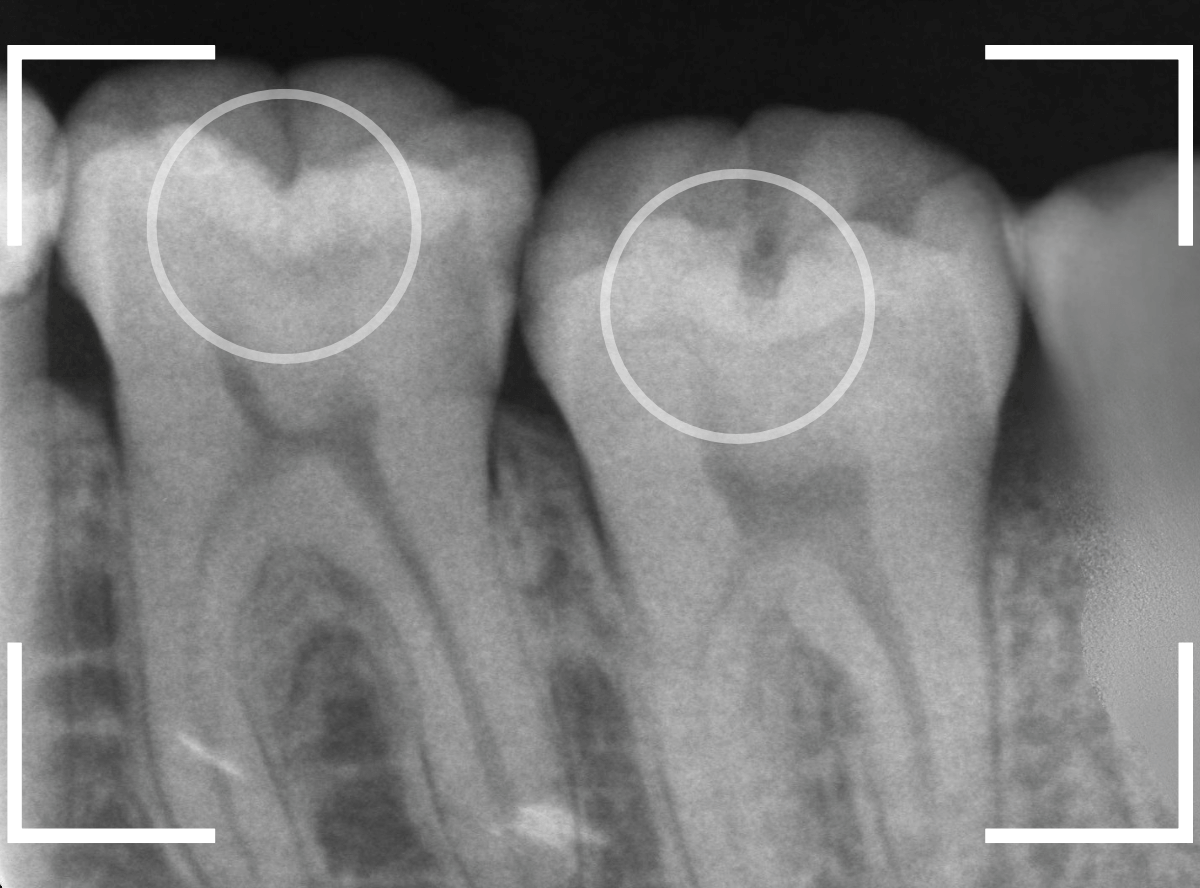

レントゲン写真で確認します。

〇部が虫歯の部分です。

左側の歯はうっすらと黒い影が見えますが、わかりづらい写り方です。

レントゲン写真で確認すると、今回はとても大きな虫歯になっている事が確認出来ました。

かなり神経の近くまで虫歯が進行しているのがわかります。

レントゲン写真で確認しますが、はっきりと虫歯は確認出来ません。

レントゲン写真で確認すると、やはり、中で虫歯が進行していました。

青い線が神経、赤い線が虫歯の部分です。

やはり、小窩裂溝の中で大きな虫歯になっています。